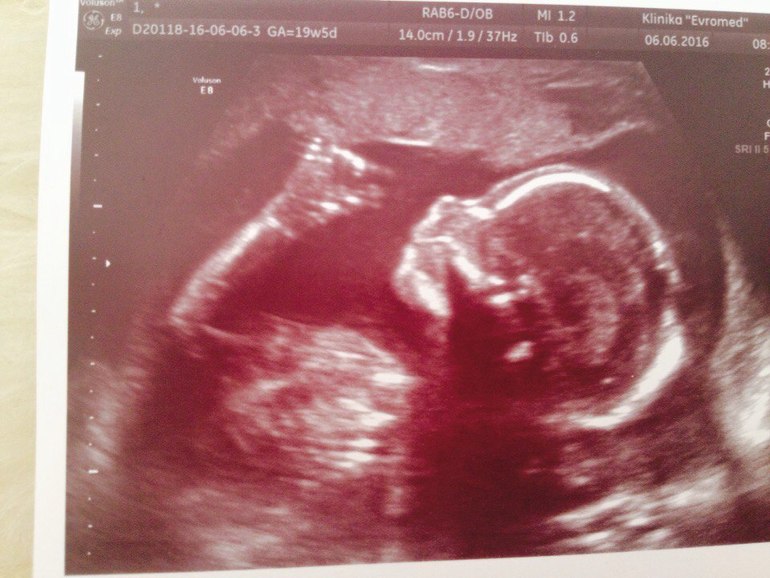

9. Новость о том, что мы ждём сыночка. Эмоции переполняли. И эти слова: у вас будет мальчик!